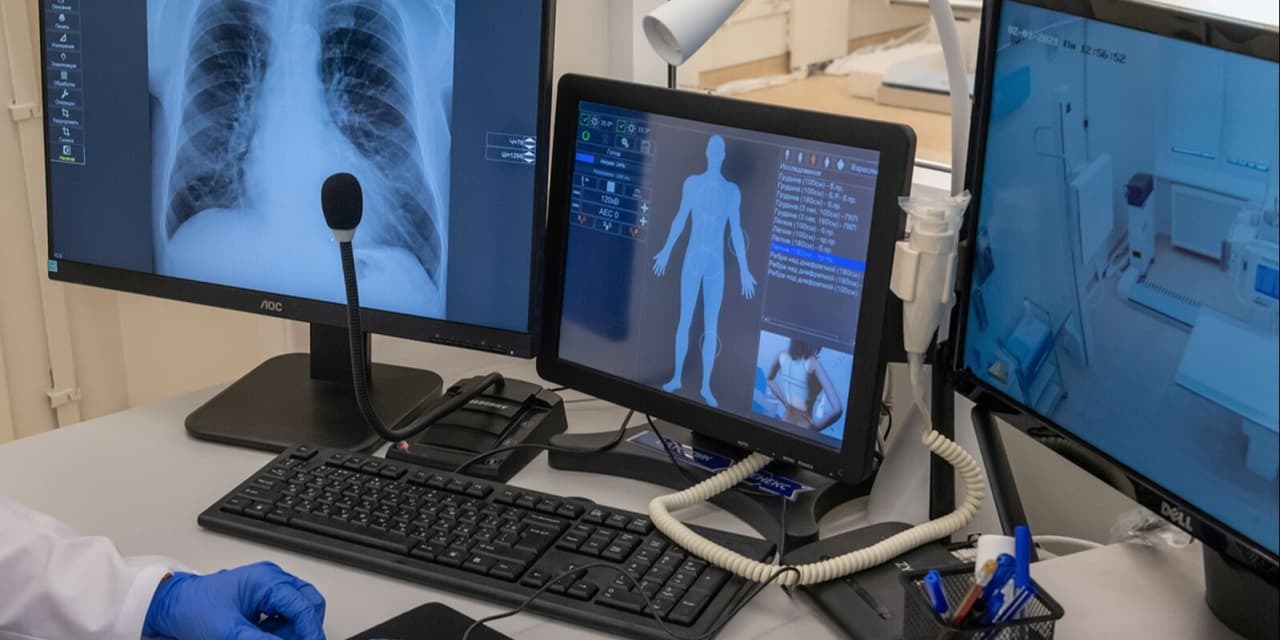

Российские ученые улучшили диагностику рака с помощью нового алгоритма

В пресс-службе Российского научного фонда (РНФ) сообщили, что российские ученые совместно с французскими коллегами разработали алгоритм, который значительно улучшит диагностику рака. Он позволяет системам компьютерного зрения более точно определять границы клеток и число их соседей на микрофотографиях клеточных слоев. ferra.ru »